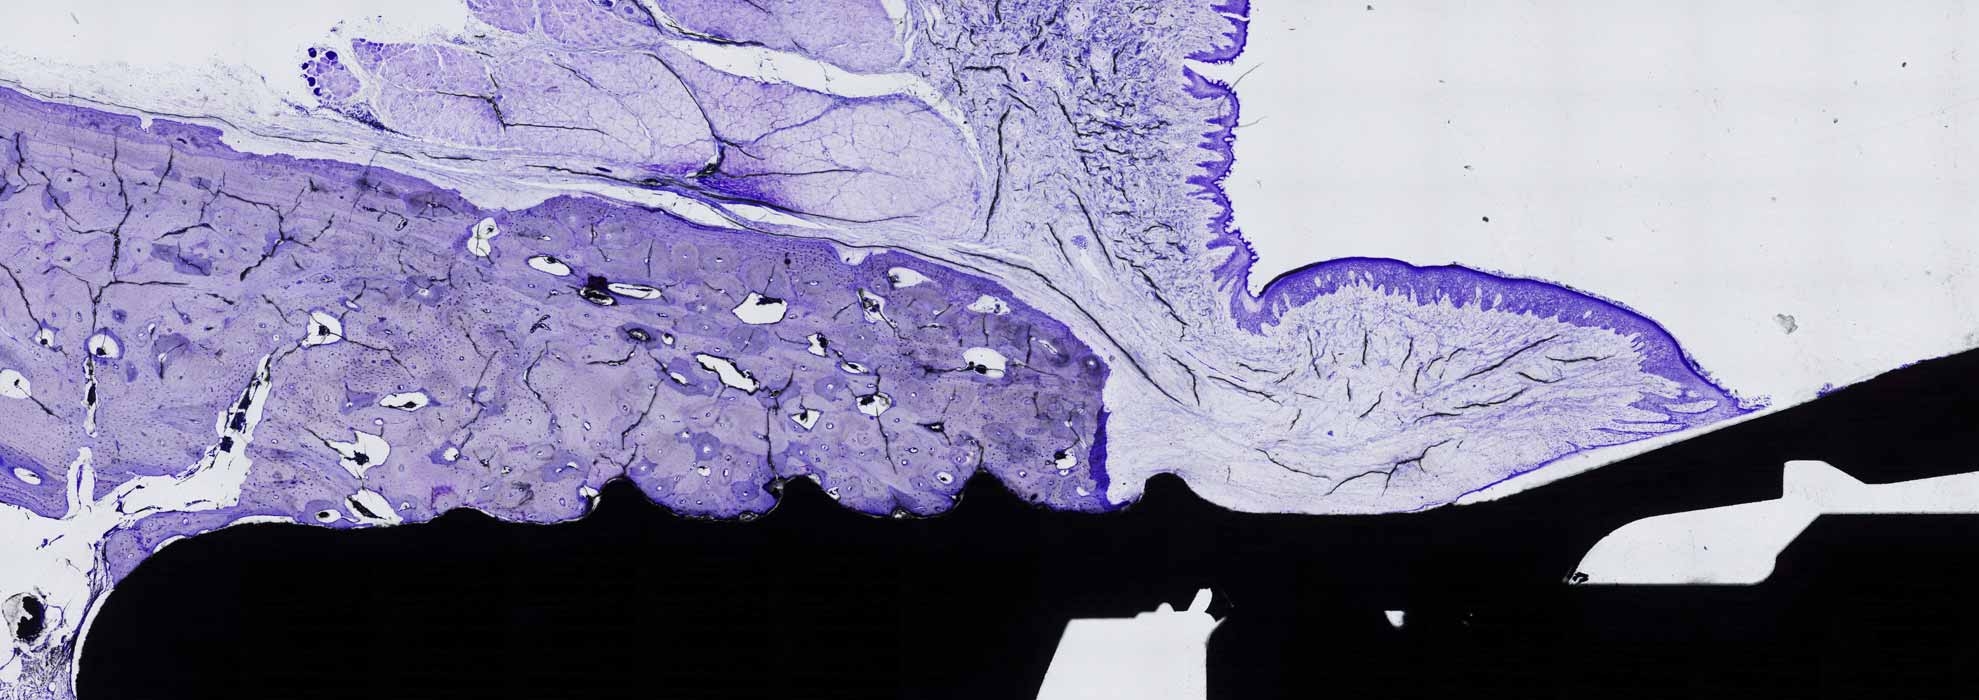

Mediante la inclusión en plástico y la técnica de lámina delgada en iBoneLab obtenemos imágenes microscópicas de alta calidad de cualquier material duro, ya sea orgánico o sintético.Más información -

Hemos optimizado la técnica histológica de “lámina delgada”, que nos permite que tanto los tejidos como los materiales implantados permanezcan inalterados para su estudio microscópico.